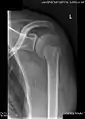

X-ray at left shows anterior dislocation in a young man after trying to get up from his bed. X-ray at right shows same shoulder after reduction and internal rotation, revealing both a bony Bankart lesion and a Hill-Sachs lesion.

Radiograph showing a bony Bankart lesion with stationary fragment at the inferior glenoid